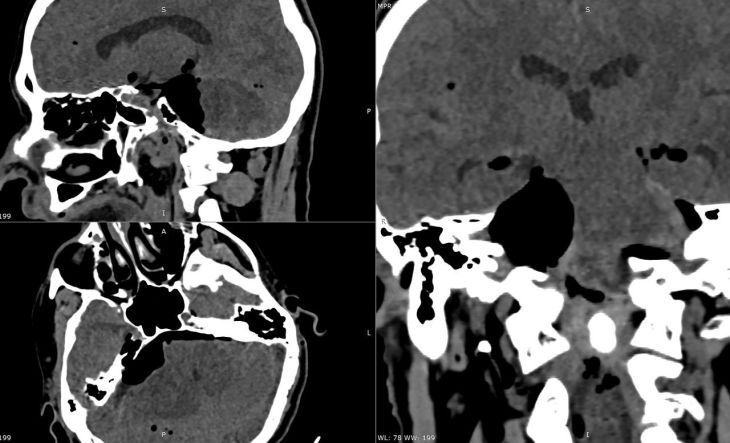

Она выросла в крошечном пространстве у основания черепа, где буквально «упакованы» жизненно важные структуры: нервы, отвечающие за мимику, зрение, глотание, дыхание, а также сам ствол мозга — центр управления жизнью.Опухоль размером с орех уже...